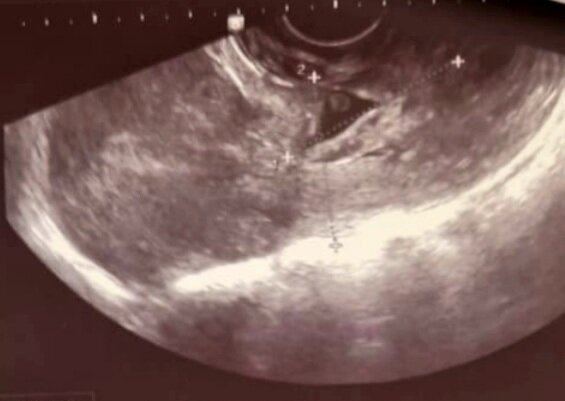

На фото- тело матки и шейка матки.  В верхней трети цервикального канала визуализируется плодное яйцо с эмбрионом.

На фото- верхняя треть шейки матки с плодным яйцом и эмбрионом.

По данным УЗИ: Матка обычных размеров, в передней стенке рубец толщиной 8,5 мм,

эндометрий- 5,2 мм.

Шейка матки бочкообразной формы, размеры 38,7 × 34,6 мм,

по передней стенке в верхней трети истончение стенки до 3,6 мм.

Цервикальный канал расширен в верхней трети , в нем определяется плодное яйцо 12,3× 7 мм, лоцируется 1 живой эмбрион, КТР- 3,6 мм- соответствует 6 неделям беременности. Регистрируется сердцебиение эмриона 175 ударов в 1 минуту, желточный мешок диаметром 2,7 мм.

Левый яичник без особенностей.

В правом яичнике " жёлтое тело " диаметром 18 мм.

Заключение: Ультразвуковые признаки прогрессирующей шеечной беременности сроком 6 недель.